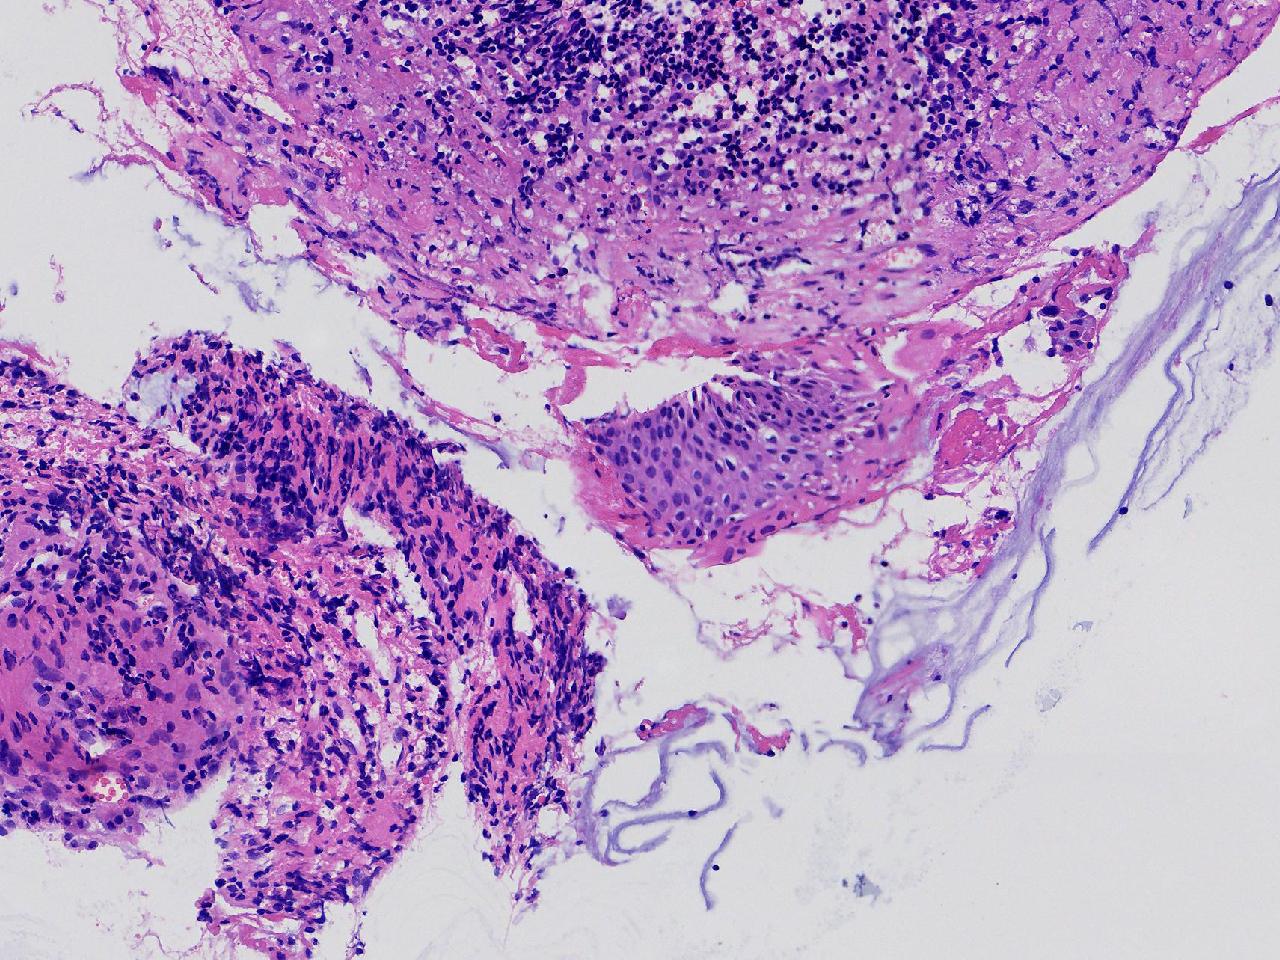

女,59岁,宫颈活检,TCT报告ASC—US, HPV不详。

宫颈多点活检。

灰白色不整形软组织多块。

CIN1,建议HPV检测

高级别